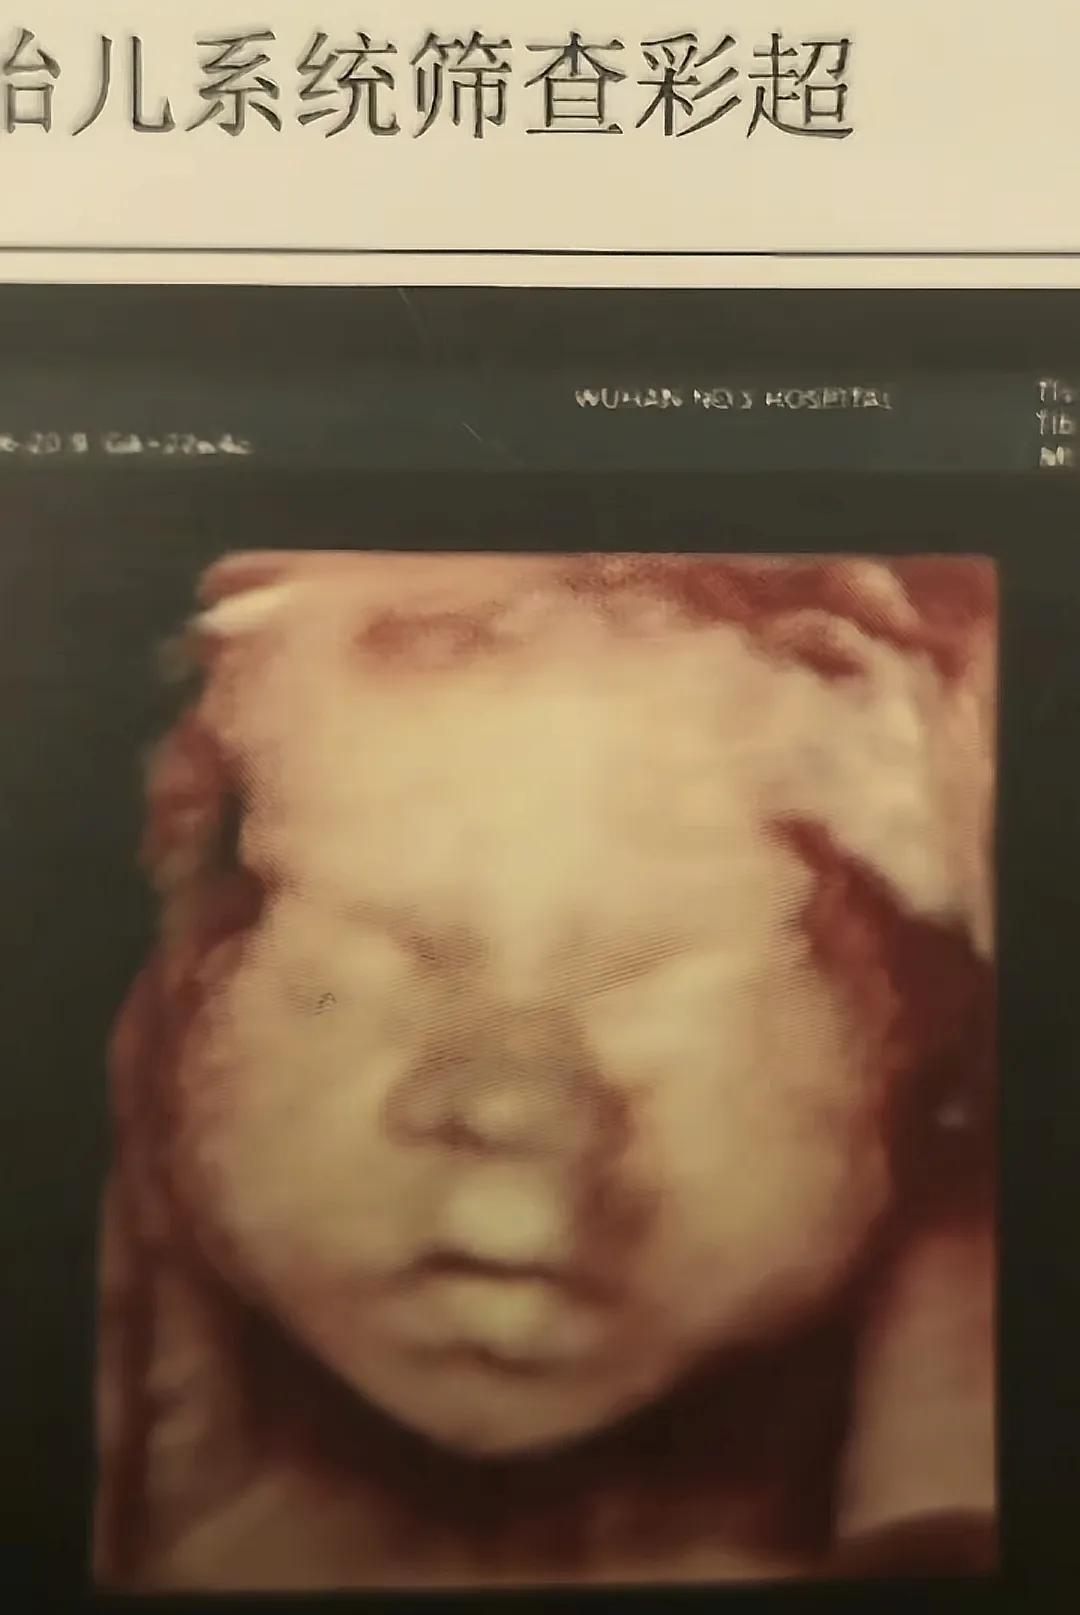

在懷孕20多周的時候就跟老婆去醫院照了個四維彩超,四維彩超會有一個彩色的圖片,圖片裏面基本能看得出孩子的五官大概像爸爸還是像媽媽。果然擔心就是詛咒,四維彩超一出來,簡直跟爸爸一個模子出來的。